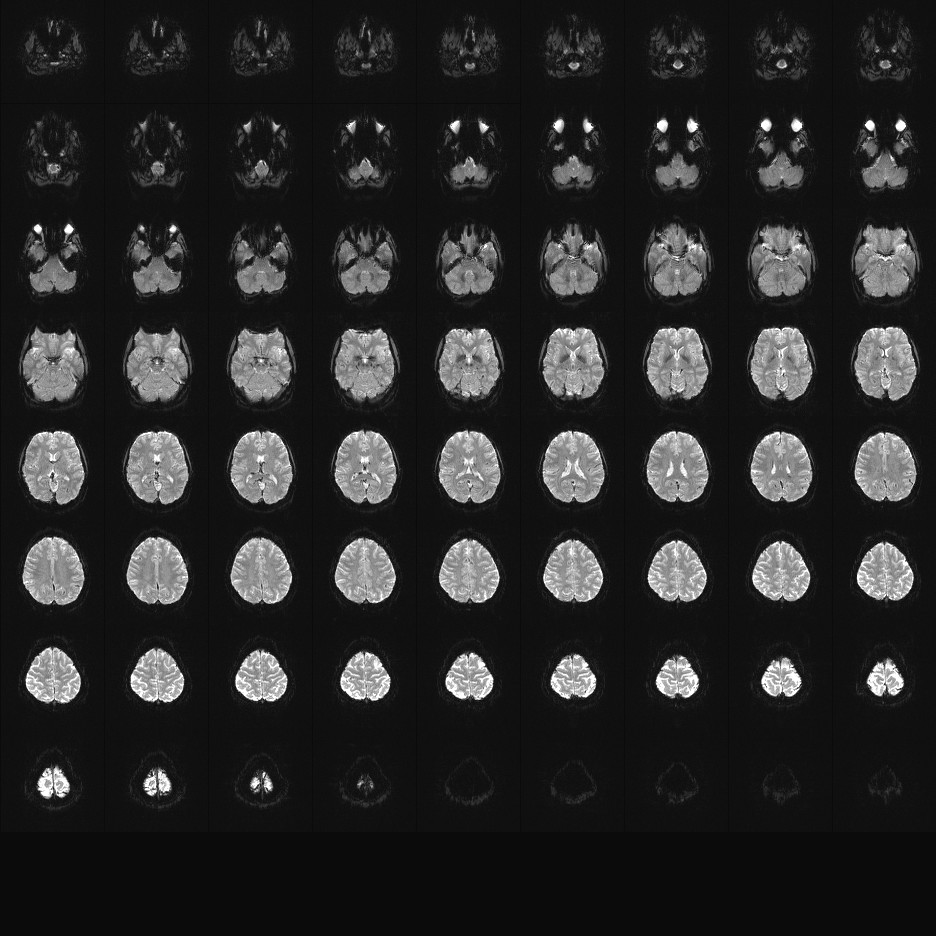

Multi-banded RF pulses can be used to accelerate volume coverage along the slice direction by simultaneously exciting and acquiring multiple slices and subsequently unaliasing them using parallel imaging principles and the spatial information available in multi-channel RF array coils.

This allows for a direct reduction in the volume TR by the number of simultaneously excited slices (i.e., the multiband (MB) factor or the slice acceleration factor).